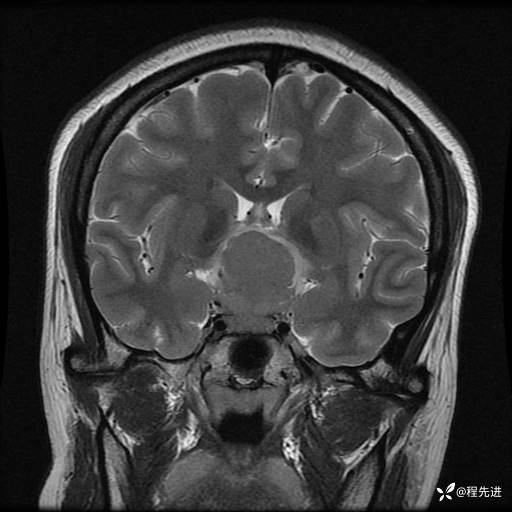

MRI平扫+增强:

T2: